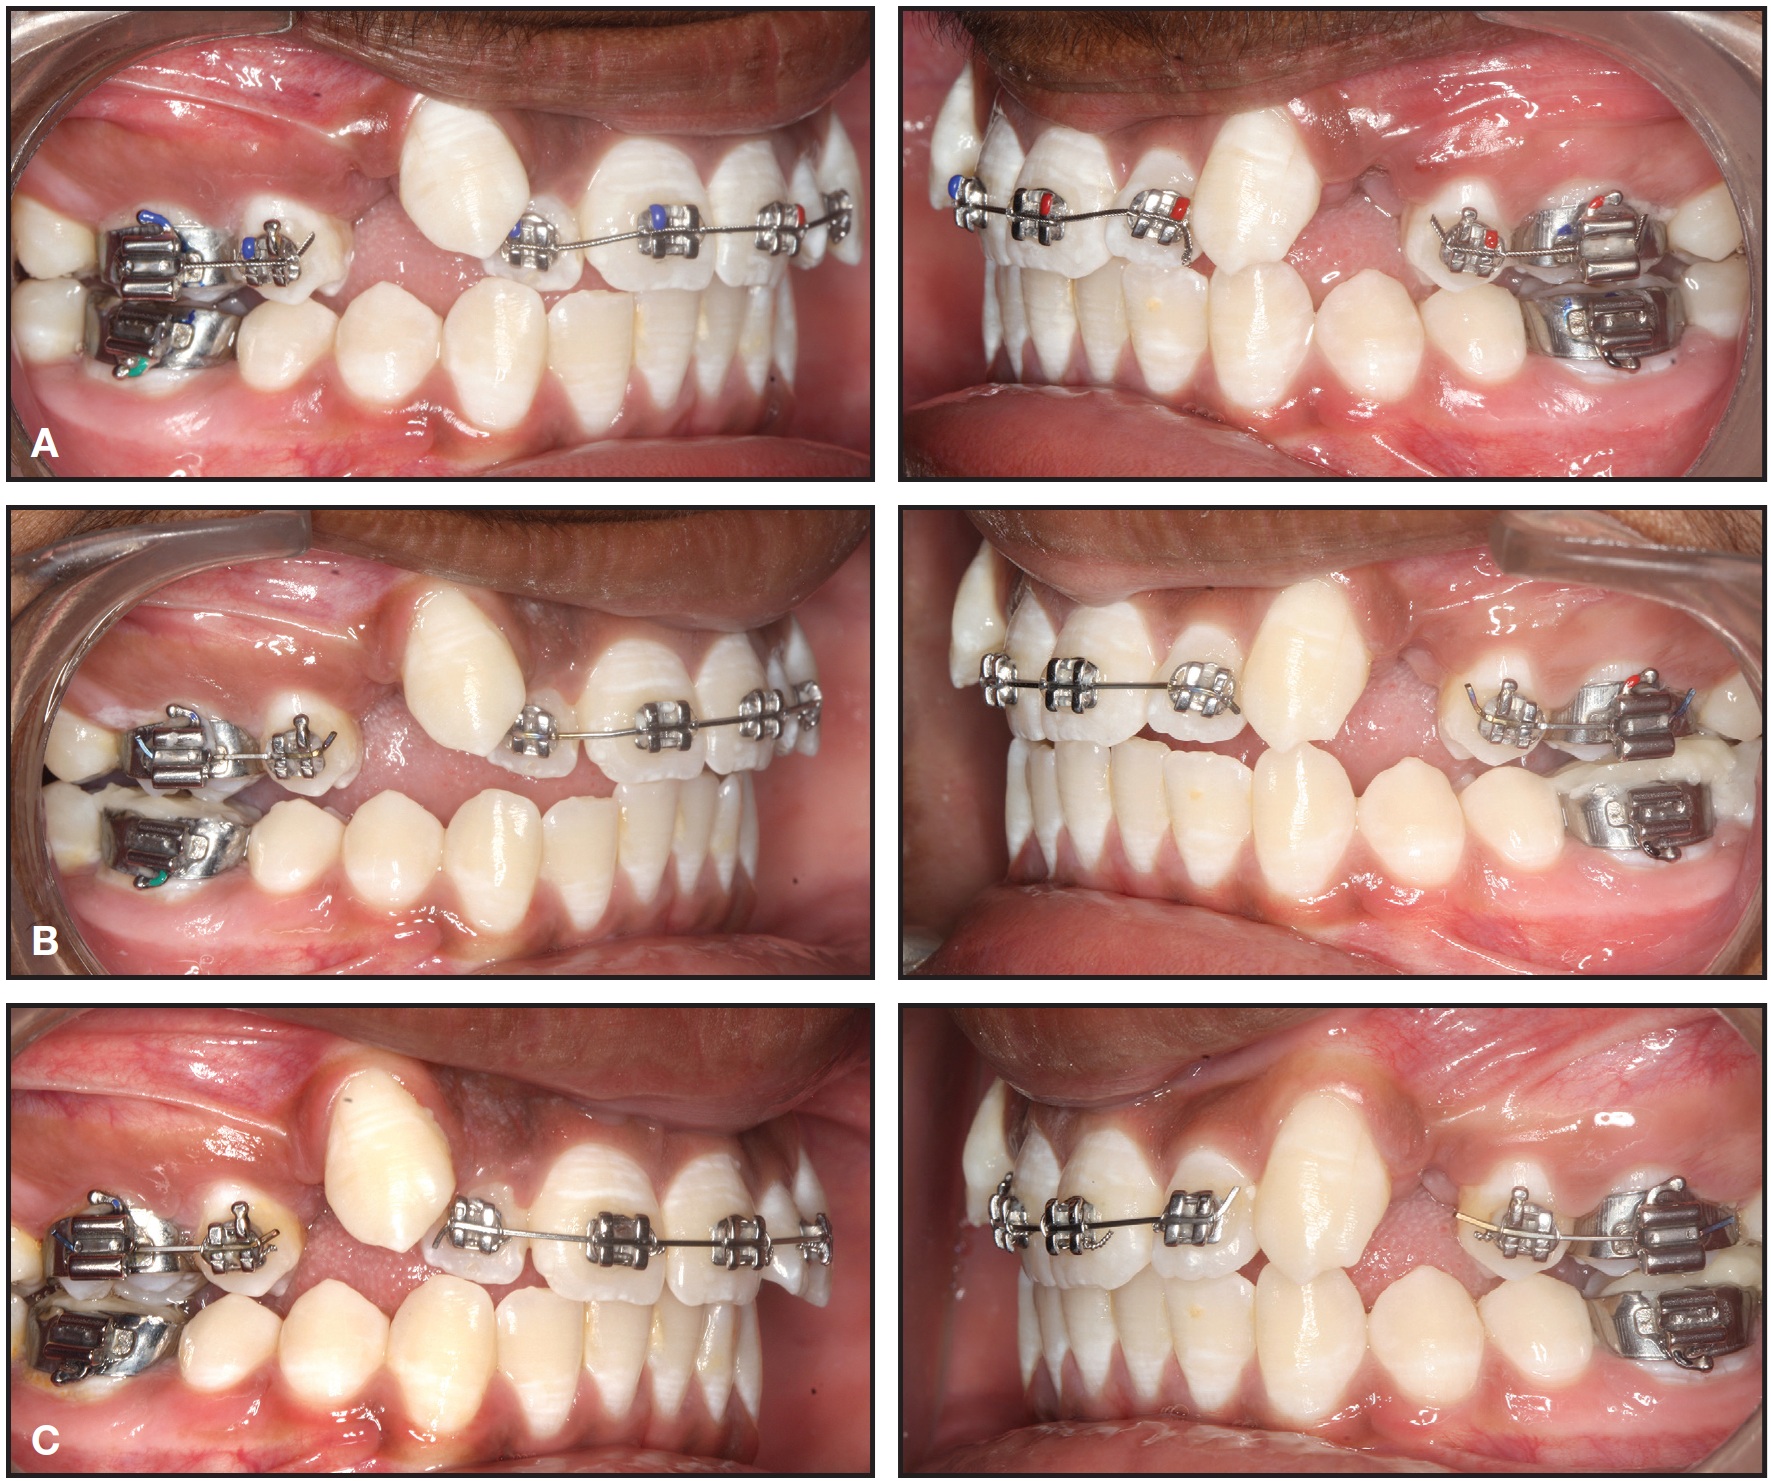

Total treatment time was 18 months. After treatment, the patient had ideal overjet and overbite, with Class II molar and Class I canine relationships (Fig. 6A). Superimposition of pre- and post-treatment cephalometric tracings confirmed a normal incisor inclination and mesialization of the upper molars (ANB = 3°, FMA = 28°, GoGn-SN = 29°, U1-SN = 104°, U1-NA = 24°/4mm, IMPA = 96°, L1-NB = 30°/6mm) and a Class II molar relationship, with no change in the vertical relationship (Fig. 6B). Fixed lingual retainers were bonded, 5-5 in the upper arch and 3-3 in the lower.

After five months of driftodontics, the upper canines and lower arch were bonded. Leveling and alignment were carried out using .014", .018", and .016" × .022" nickel titanium and .016" × .022" and .017" × .025" stainless steel archwires. Space closure was completed using sliding mechanics on .019" × .025" stainless steel archwires with Class III elastics. Finishing, detailing, and settling were accomplished using .014" stainless steel archwires and red elastics (3⁄16", 3.5oz).

Fig. 6 Case 2. A. Patient after 18 months of treatment. B. Superimposition of pre- and post-treatment cephalometric tracings.